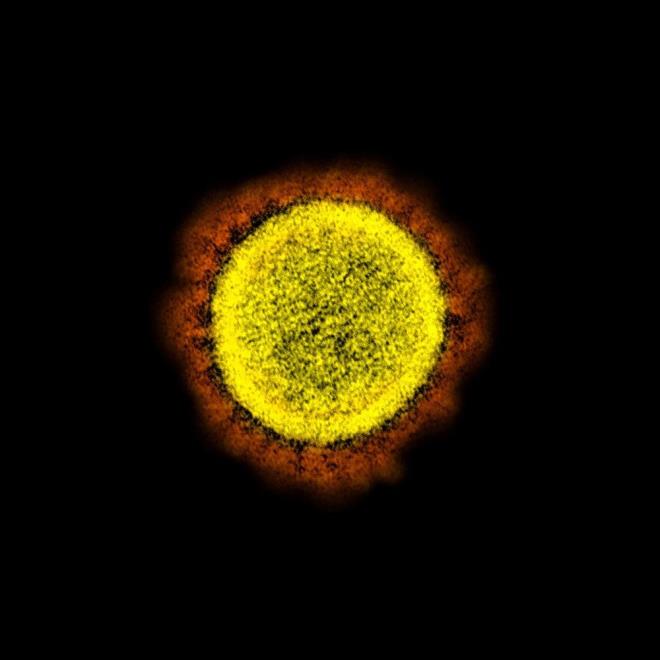

4. Burada bir tarama elektron mikroskobu altında görülen yuvarlak sarı nesneler, Kovid-19'a neden olan virüsleri gösteriyor.

Burada bir tarama elektron mikroskobu altında görülen yuvarlak sarı nesneler, Kovid-19'a neden olan virüsleri gösteriyor.